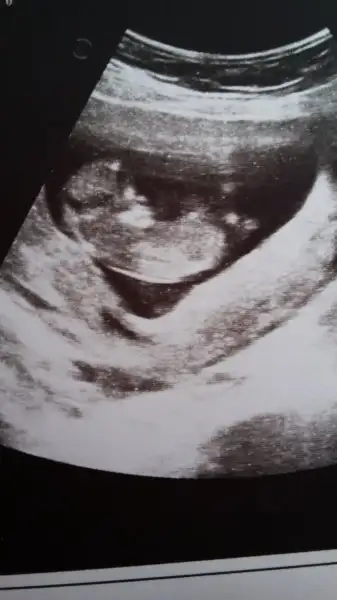

Senin bebekkini göremedim nubu yok nubsuz buHerkes bebisinin fotosunu yukleyip tahmin istemis ben de 2.gebeligim olmasina ragmen tahminde bulunamiyorum ve nub nedir bilmiyorum. Bana da yorumlar misiniz merak ediyorum acikcasi

Sakliyor sanirim gizemli olacakSenin bebekkini göremedim nubu yok nubsuz bu

Beli düz yere yatay sekilde duruyosa kız.Bişi diğil

Beli düz yere yatay sekilde duruyosa kız.

Yukarı dogru kalkık ise erkek.

Bole yorumluyolar yani